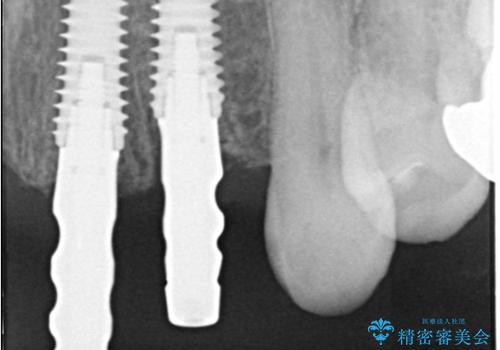

- 歯茎の大きな腫れを主訴に来院された患者様です。前歯5本にはブリッジが装着されていました。レントゲン検査より、右上3番に大きな根尖病巣が認められ、さらに左上1、2番の支台歯にも破折があったため、抜歯を行いました。その後、インプラントを3本埋入し、オールセラミッククラウンのブリッジで補綴しました。

術前のCT画像より、抜歯即時インプラントが可能と判断したため、抜歯と同時にインプラント埋入を行いました。術式にはセミルーナーフラップを用い、唇側の骨吸収を抑える目的でルートメンブレンテクニックを併用しました。

抜歯即時インプラントには、切開量が少なく痛みが出にくいこと、一度の手術で治療が完了するため治療期間を短くでき、患者様の身体的負担も軽減できるという大きなメリットがあります。

今回のケースでも、しっかりと固定が得られたため、手術は1回で終了し、短期間でオールセラミッククラウンまで装着することができました。患者様も術後の痛みはなく、処方した痛み止めも服用されなかったとのことです。